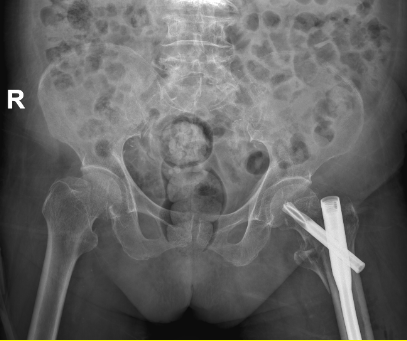

征得患者及家属同意后,手术当日,骨科一区医护团队密切配合,在C型臂X线机的精准引导下,仅通过几个微小切口,便顺利完成骨折闭合复位和内固定植入,手术过程顺利,出血量少,手术时间短。术后,莫婆婆生命体征平稳,被安全送回普通病房。

术前与术后